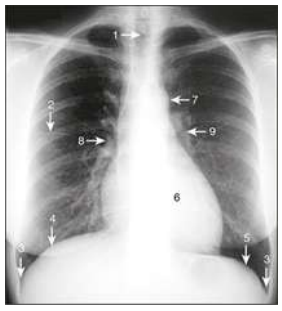

Observe a radiografia de tórax e associe os números indicados na imagem às estruturas anatômicas listadas:

Enunciado 4661067-1  OLIVEIRA, Rafael Carvalho Rezende. Fisioterapia respiratória. 3. ed. Rio de Janeiro: Guanabara Koogan, 2022. il.

(__)Hemidiafragma direito

(__)Hilo esquerdo

(__)Arco aórtico

(__)Traqueia

(__)Ângulo costofrênico

Assinale a alternativa que apresenta a sequência correta: